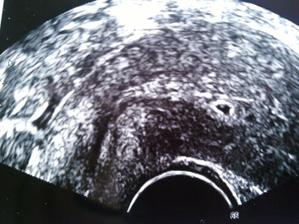

tak tu je drobcek ma 2mm